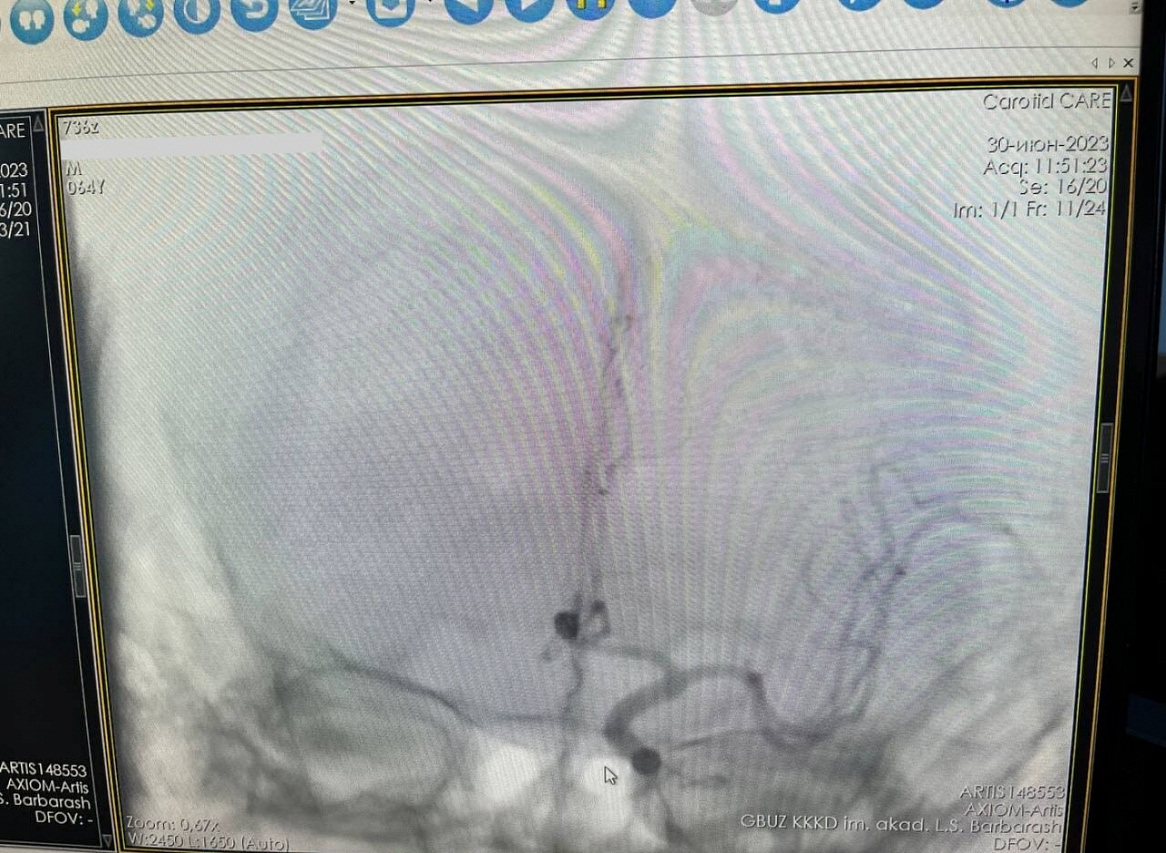

Разрыв аневризмы у пациента отличался сложной анатомией, недоступной открытой хирургии, поэтому был применен метод эмболизации. Преимущество эндоваскулярной эмболизации для пациента в том, что это малоинвазивное операционное вмешательство, которое заключается в выключении аневризмы из кровотока сосудов головного мозга с использованием специального материала, без разрезов, с минимальным реабилитационным периодом. С учетом подготовительных мероприятий операция длилась около двух часов.

Данная высокотехнологичная операция была проведена на новом ангиографическом комплексе Siemens, который поступил в Кузбасский кардиодиспансер по нацпроекту «Здравоохранение».